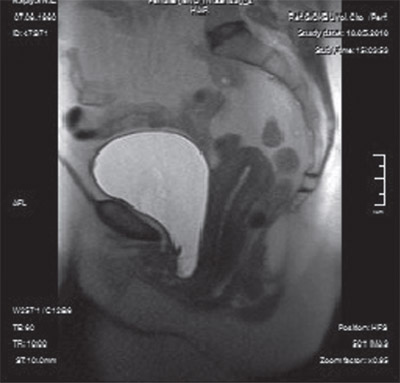

Степень опущения мочевого пузыря, уретры, влагалища и матки определя ли по смещению их относительно линии, соединяющей нижний край лонного сочленения и копчик (лонно-копчиковая линия, рис. 1 и 2).

Результаты и обсуждение. МРТ и МСКТ, полученные у больных со СНМ в сагиттальной плоскости в спокойном состоянии и на высоте пробы Вальсальвы, позволили оценить и документировать степень опущения пузырно-уретрального сегмента в см относительно лонно-копчиковой линии (рис. 1, 2 и 3).

Рис. 2 Магнитно-резонансная томограмма таза той же больной что и на рис. 1, выполненная на высоте пробы Вальсальвы. Смещение пузырно-уретрального сегмента и средней части влагалища ниже лонно-копчиковой линии. (Опущение передней стенки влагалища с формированием цистоцеле.)